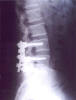

Osteoporosis. Cifosis.

Escoliosis, artrosis, aplastamiento...